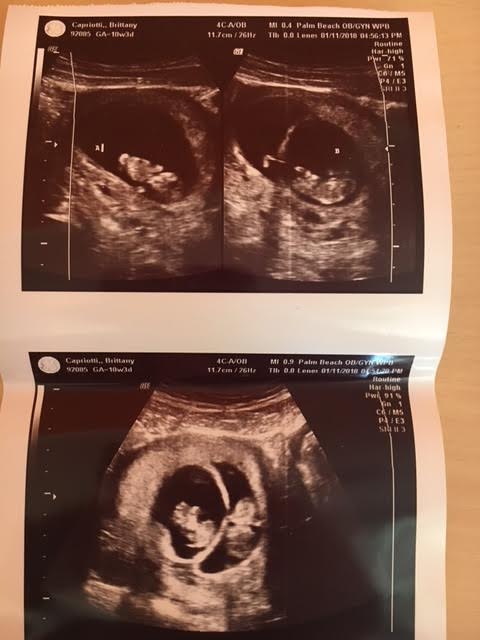

Ultrasound Photos of 10 Weeks Pregnant With Twins